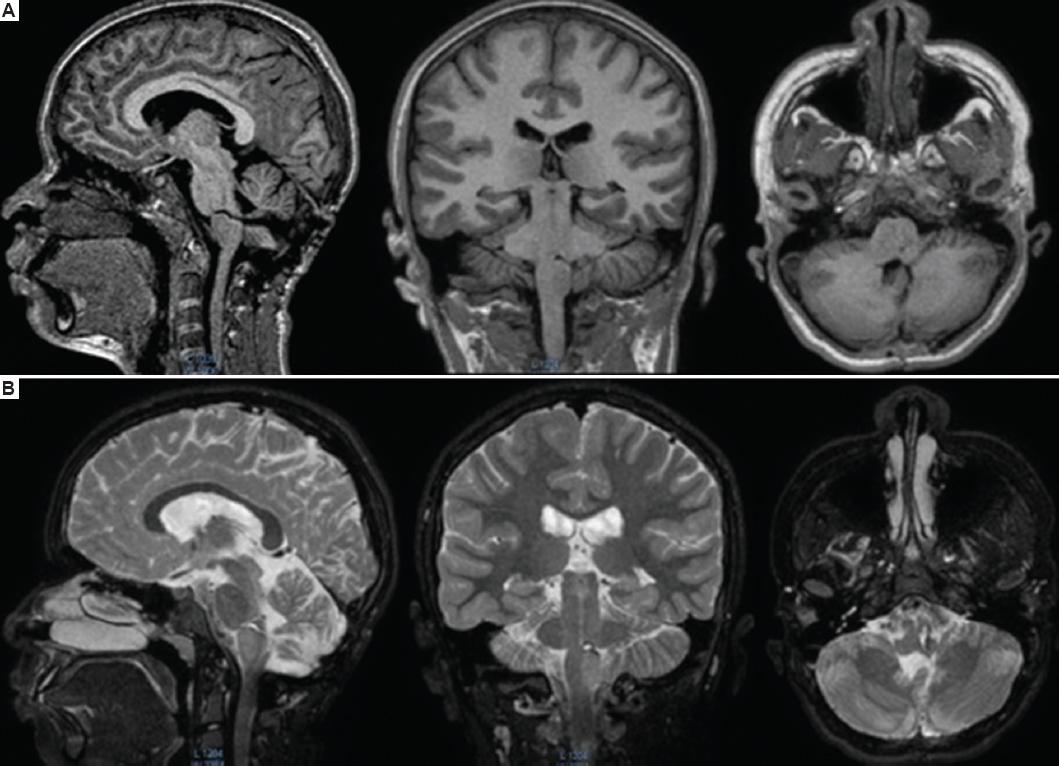

Presentamos el caso de una niña de 10 años que 7 días previos a su ingreso tuvo cefalea y pérdida transitoria del estado de consciencia con posterior recuperación, y desarrolló hemiparesia en el hemicuerpo derecho con fuerza 2/5, ataxia y afección de los nervios craneales izquierdos VI, VII, IX y X. Se le realizó una tomografía de cráneo simple y fue enviada a nuestro hospital para valoración por neurocirugía pediátrica, complementando su abordaje con RM de encéfalo y columna, que evidenció una lesión intraaxial, subpial del tallo cerebral en la unión pontobulbar izquierda, sugestiva de una MC (Fig. 1). Se realizó cirugía a los 10 días de iniciada la sintomatología. Con la paciente en decúbito prono, bajo monitorización neurofisiológica intraoperatoria y con técnicas de microcirugía, se realizó un abordaje telovelar, localizando el piso del ventrículo IV y el colículo facial izquierdo, presentando el colículo un incremento de volumen y un halo de hemosiderina. Se hizo una incisión infracolicular, obteniendo material hemático antiguo, y se identificó una MC de 7 mm que fue resecada totalmente, se corroboró la hemostasia y se cerró por planos de manera convencional (Fig. 2). La paciente fue extubada a las 72 horas. Al persistir con dificultades para la deglución, requirió una gastrostomía endoscópica. Fue egresada a su domicilio a los 7 días del posoperatorio. Se le dio seguimiento en la consulta externa, confirmando el diagnóstico de MC por histopatología. A los 4 meses logra deambular de forma independiente, con una fuerza 4/5 en el hemicuerpo derecho, resolución de la parálisis facial y capacidad de deglución, y se le retira la gastrostomía por lograr un adecuado peso para su talla y edad; aún persistía afección del VI nervio craneal izquierdo. Al año de la cirugía recupera totalmente la fuerza del hemicuerpo derecho y la función de los nervios craneales. Se realiza una RM de encéfalo de control que evidencia la ausencia de la MC (Fig. 3). La paciente no tiene antecedentes de exposición a radiación ni historia familiar de MC, y se descartó una alteración genética.

Figura 3 Resonancia magnética posoperatoria en secuencias T1 (A) y T2 (B), en cortes sagital, coronal y axial, que evidencian la ausencia de la lesión en la unión pontobulbar izquierda (compárese con la figura 1).